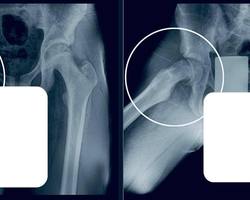

В ходе обследования выяснилось, что у подростка – юношеский эпифизеолиз.

Патология подразумевает смещение головки бедренной кости, характерное для периода активного роста скелета.

— Пациенту требовалась срочная операция. Мы выполнили фиксацию сустава, чтобы остановить смещение и дать ему возможность правильно развиваться. Это убережет юношу от раннего артроза и ограничений подвижности в будущем, — отметил главный врач МОДКТОБ Александр Григорьев.